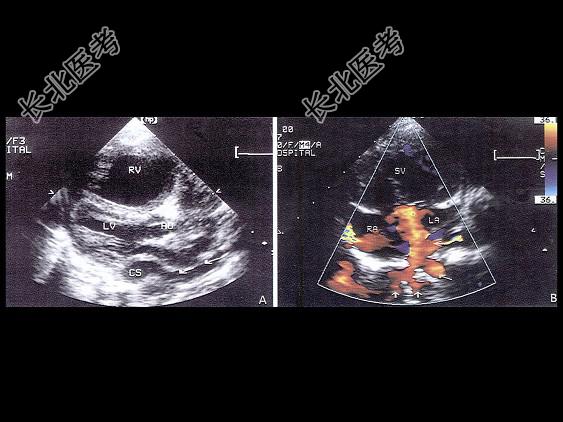

- 单项选择题该病例最可能的诊断为 ( )

A、肺静脉畸形引流入上腔

B、肺静脉畸形引流入右心房

C、肺静脉畸形引流入下腔

D、肺静脉畸形引流入冠状窦

E、以上都不是